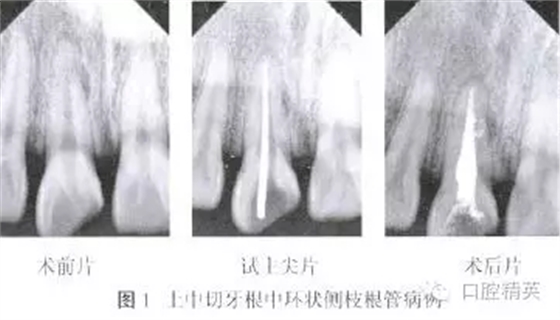

患者,男,24歲,因右上頜中切牙破損、變色10余年,近1個月反復(fù)出現(xiàn)牙齦腫脹、瘺管,咬合疼痛等癥狀。于2013年7月就診。檢查:右上中切牙牙冠色暗,切端近中斜折,髓腔暴露,內(nèi)有少量腐質(zhì),叩痛(+),無松動,頰側(cè)牙齦距離齦緣3mm處可見瘺管。瘺管處牙齦腫脹約2mm×2mm。X線片示根管內(nèi)無充填物,根中近中側(cè)可見弧形低密度影像,根尖周圍低密度影像(圖1)。

拍攝X線片根中遠中側(cè)可見兩個側(cè)枝根管充填后形成的環(huán)形影像(圖1)。氧化鋅嚴密封填,擬觀察2周后行樁核冠修復(fù)。以上所有治療均得到患者知情同意。